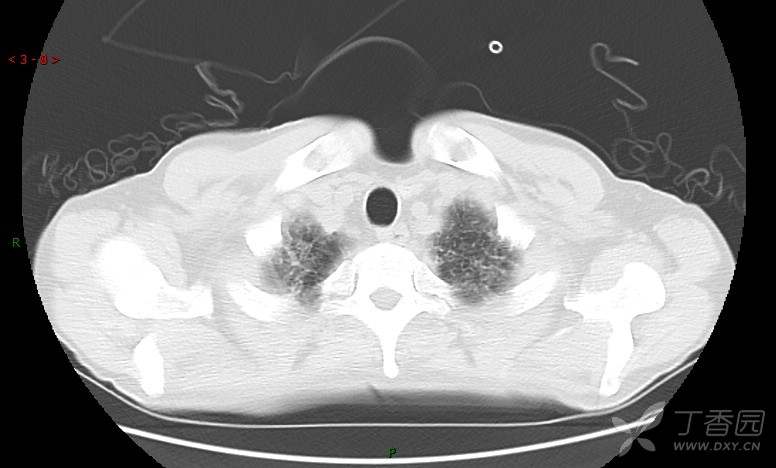

患者男,42岁,咳嗽半年余,加重伴憋喘2月余。

患者半年余前无明显诱因出现间断咳嗽,干咳为主,偶咳少量黄白痰,剧烈咳嗽或运动后可出现轻度憋喘,无高热、脓臭痰,无胸痛、咯血及晕厥,无低热乏力及盗汗,无心前区压榨感及夜间阵发性呼吸困难,初未在意,未予正规诊治。2月余前患者自觉上述症状较前加重,咳嗽、憋喘明显,黄白色粘痰略有增多,伴有发热,热前伴有畏寒、寒战,体温最高达38.9℃,先后就诊多家医院,入住重症监护室,未行气管插管,考虑“重症肺炎”,给予“美罗培南、复方磺胺甲噁唑”等药物抗感染,“卡泊芬净”抗真菌,并给予“甲泼尼龙”等药物治疗35天,经治疗后症状好转于2018-04-02出院。患者自出院后仅应用中药治疗(具体不详),并给予家庭氧疗,平素仍有间断咳嗽,咳少量黄白色粘痰,活动后憋喘明显,活动耐量差,以卧床为主。